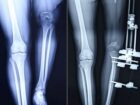

中国人女性、1年で脚を23cm伸ばすことに成功! 1日1mmまで!? 仰天治療!...

もっと長い脚をもっていたら……そう夢見る人は多い。し...